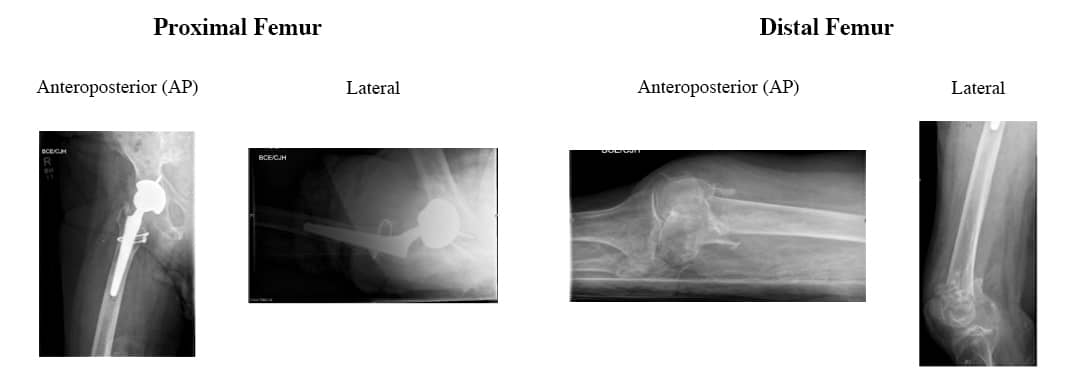

As incidências anterioposterior (AP) e lateral pré-operatórias do fêmur proximal e distal demonstram uma prótese ATQ intacta e uma fratura cominutiva e impactada do fêmur distal.